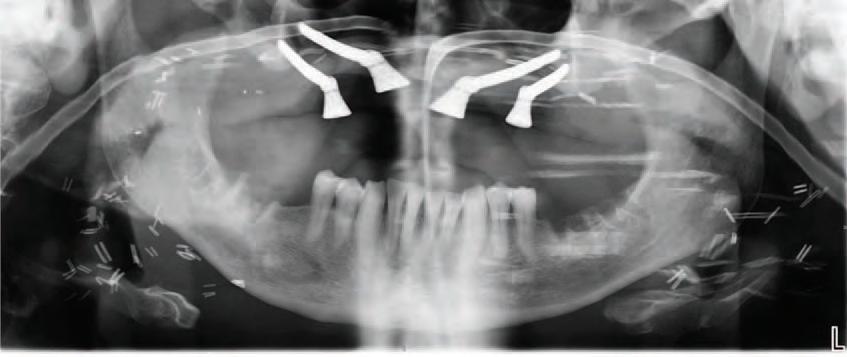

The zygomatic implant perforated (ZIP) flap for rehabilitation of patients with midfacial oncology defects: a report of three cases B. Martin, E. Cotter, C. Bowe, J.E. O’Connell

145 CLINICAL FEATURE